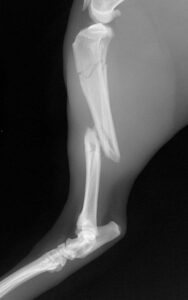

Pet Orthopaedic Surgery – Xray

Pet Orthopaedic Surgery